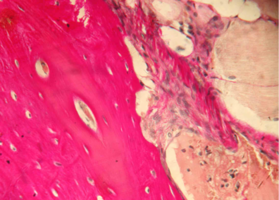

Репаративные процессы на 14 сутки после пластики костного дефекта смесью лиофилизированной аллоспонгиозы и ГАП 1:1.

На обзорной микрофотографии при малом увеличении (х100) видна зона вмешательства, содержащая имплантированный композит, представляющий собой смесь аллогенных спонгиозы и ГАП (рис. 2).

После проведенной предварительной деминерализации костей нижней челюсти в процессе стандартной гистологической проводки кристаллы ГАП в большинстве своем подвергаются растворению, поэтому не видны на препаратах либо видны лишь в единичных случаях.

На их месте чаще всего обнаруживаются округлой либо овальной формы пустоты в костном веществе имплантированной спонгиозы или в прилежащей к зоне пластики соединительной ткани.

Область вмешательства окружена интактной костью нижней челюсти и прилежащими соединительной и мышечной тканями.

Аллогенная спонгиоза в зоне пластики визуализируется в виде безъядерной субстанции костного строения, имеющей губчато-ячеистую структуру.

Содержит множество округлой, овальной и неправильной формы ячеек, заполненных соединительной тканью.

Костный компонент спонгиозы интенсивно окрашивается в ярко-красный (при окраске пикрофуксином по Ван Гизон) или ярко-розовый (при окраске гематоксилином и эозином) цвет.

Рис. 2. Нижняя челюсть кролика через 14 суток после остеопластики слева, смесь лиофилизированной аллоспонгиозы и ГАП 1:1.

Область пластики, заполненная имплантатом аллогенной спонгиозы, обозначена черными стрелками.

Синими стрелками указана интактная кость.

Окраска - пикрофуксин по ван Гизон, х100.